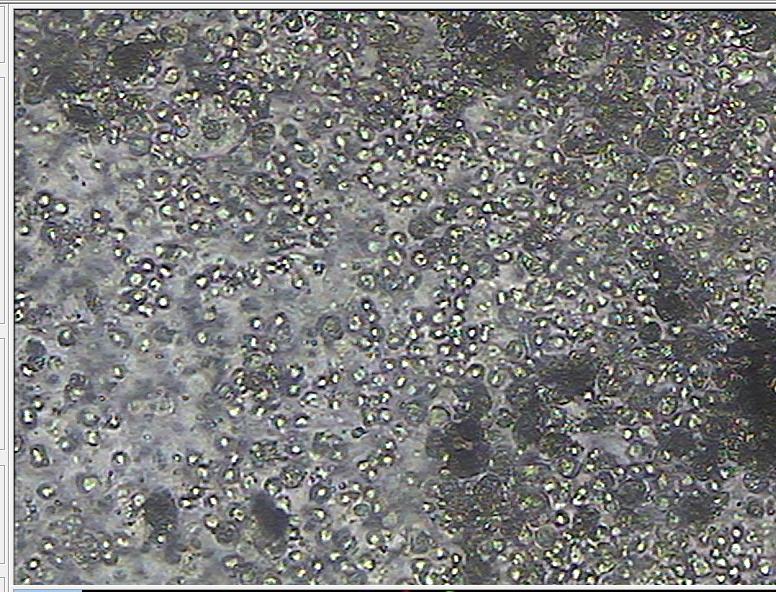

(显微镜下的白细胞)

(显微镜下可见:白细胞大于10个/HP)

(显微镜下可见:脓细胞团,提示前列腺有明显感染)

(显微镜下见:白细胞4+?脓球4+?10倍视野)